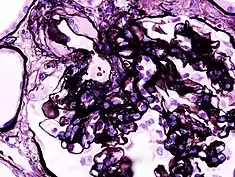

_PAM.jpg.webp)

Secondary causes of nephrotic syndrome have the same histologic patterns as the primary causes, though they may exhibit some differences suggesting a secondary cause, such as inclusion bodies.[24] They are usually described by the underlying cause, such as: